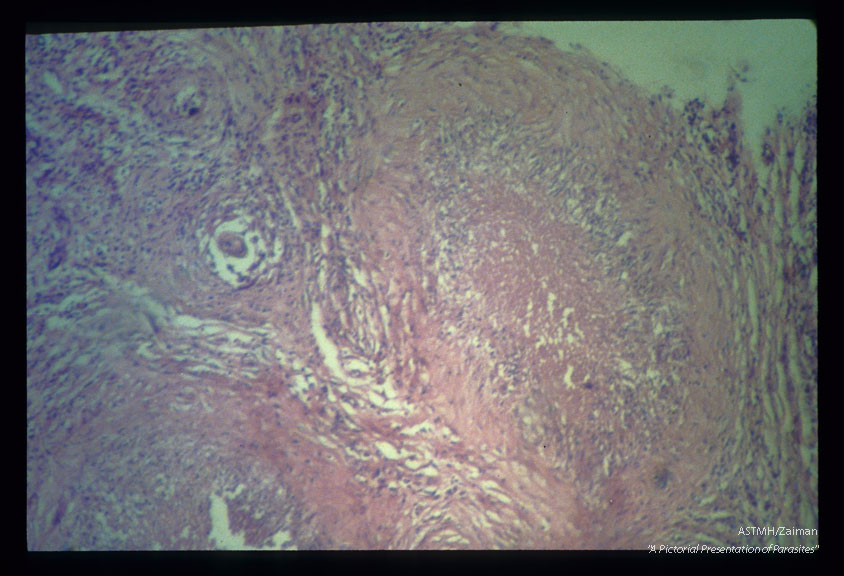

Gross and microscopic photos showing granulomatous formations in testicle as well as adult worm in the pampiniform plexus.

Schistosoma mansoni

Description: Gross and microscopic photos showing granulomatous formations in testicle as well as adult worm in the pampiniform plexus.